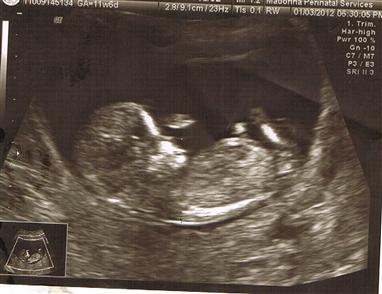

Re: ultrascreen---nub guesses-more pics!

Thanks for yourguesses...I added more pics...hopefulyy they are better!